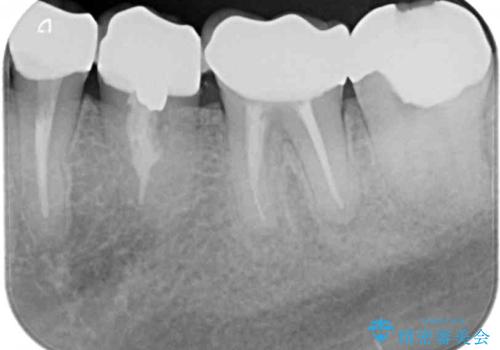

右上の歯は噛んだときに何カ所か痛みを感じるとのことで、診査したところ第二小臼歯が患歯と疑われました。

患者様は他の歯にも痛みを感じるとおっしゃっていましたが、そのような所見が認められなかったため、まずは第二小臼歯を処置し、その痛みが引いた後に再診査することとしました。